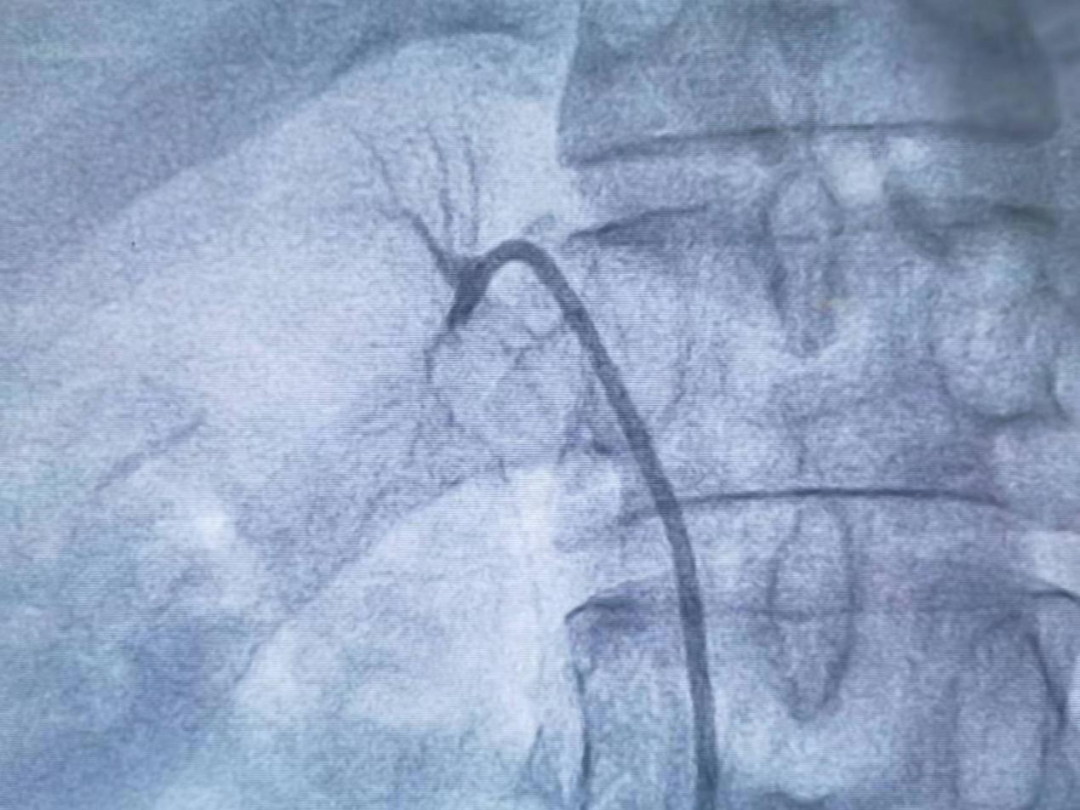

经典的AVS一般采用股静脉入路,近年国家心血管病中心阜外医院蒋雄京教授发展了经肘静脉的入路,使AVS的学习曲线明显缩短。既往的AVS无论是股静脉入路还是肘静脉入路,均需应用2种或以上的采血导管,采血的成功率和效率仍无法让人满意。

近年,成都医学院第一附属医院心血管内科高血压中心王沛坚教授团队经股静脉入路第一次介绍了一根导管法进行AVS 100余例的报道。

在此之后工作中,王沛坚教授不断改进方法和总结经验,在原来方法基础上进行了改良,90%以上的患者可在10min之内成功完成采血,目前中心已采用该技术完成近500例的AVS,是全球范围内较为成熟的AVS中心。

该方法不但减少了患者和术者的射线暴露,还显著提高了采血的效率和成功率并在最大程度上节约了卫生耗材。王沛坚教授的改良一根导管法行AVS在国内多个学术会议和多个医院进行了推广,得到了同行的认可。